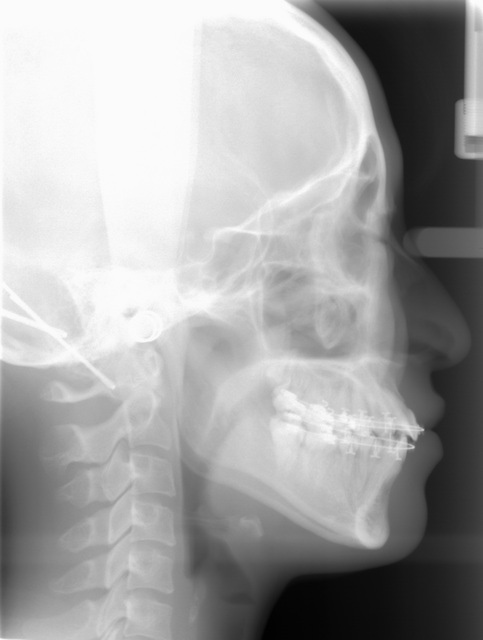

セファロレントゲン(頭部X線規格写真)

一定の規格に基づいて撮影されるレントゲンのことをセファロレントゲン(頭部X線規格写真)といいます。 長期間に及ぶ矯正治療では必要不可欠なものであり、噛み合わせの状態や顔の骨格を調べるだけでなく初診検査時から治療中や治療後を正確に比較することが可能です。 当院では1.0秒以下でワンショット撮影が可能な機種を導入しておりますので、被曝量も低減され、患者様の体動による影響もないため快適な撮影が可能です。